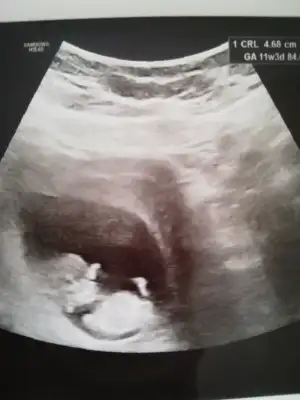

Kız gibi gibi diyorum net degil başka usg varsa tekrar tahmin ederimMerhaba bunlar da benim ultrason görüntülerim, yorumlar mısınız rica etsem. 11+3'deyiz![]()

Kız gibiMerhaba hanımlar, şimdi dr.dan geldim adete göre 10+6 ultrasona göre 11+6, banada cinsiyet tahmini yapar mısınız rica etsem?

Çok teşekkür ederim tüm ultrason görüntülerini paylaştım 10 gün sonra tekrar gideceğim inşallah doktorum da kız derKız gibi gibi diyorum net degil başka usg varsa tekrar tahmin ederim